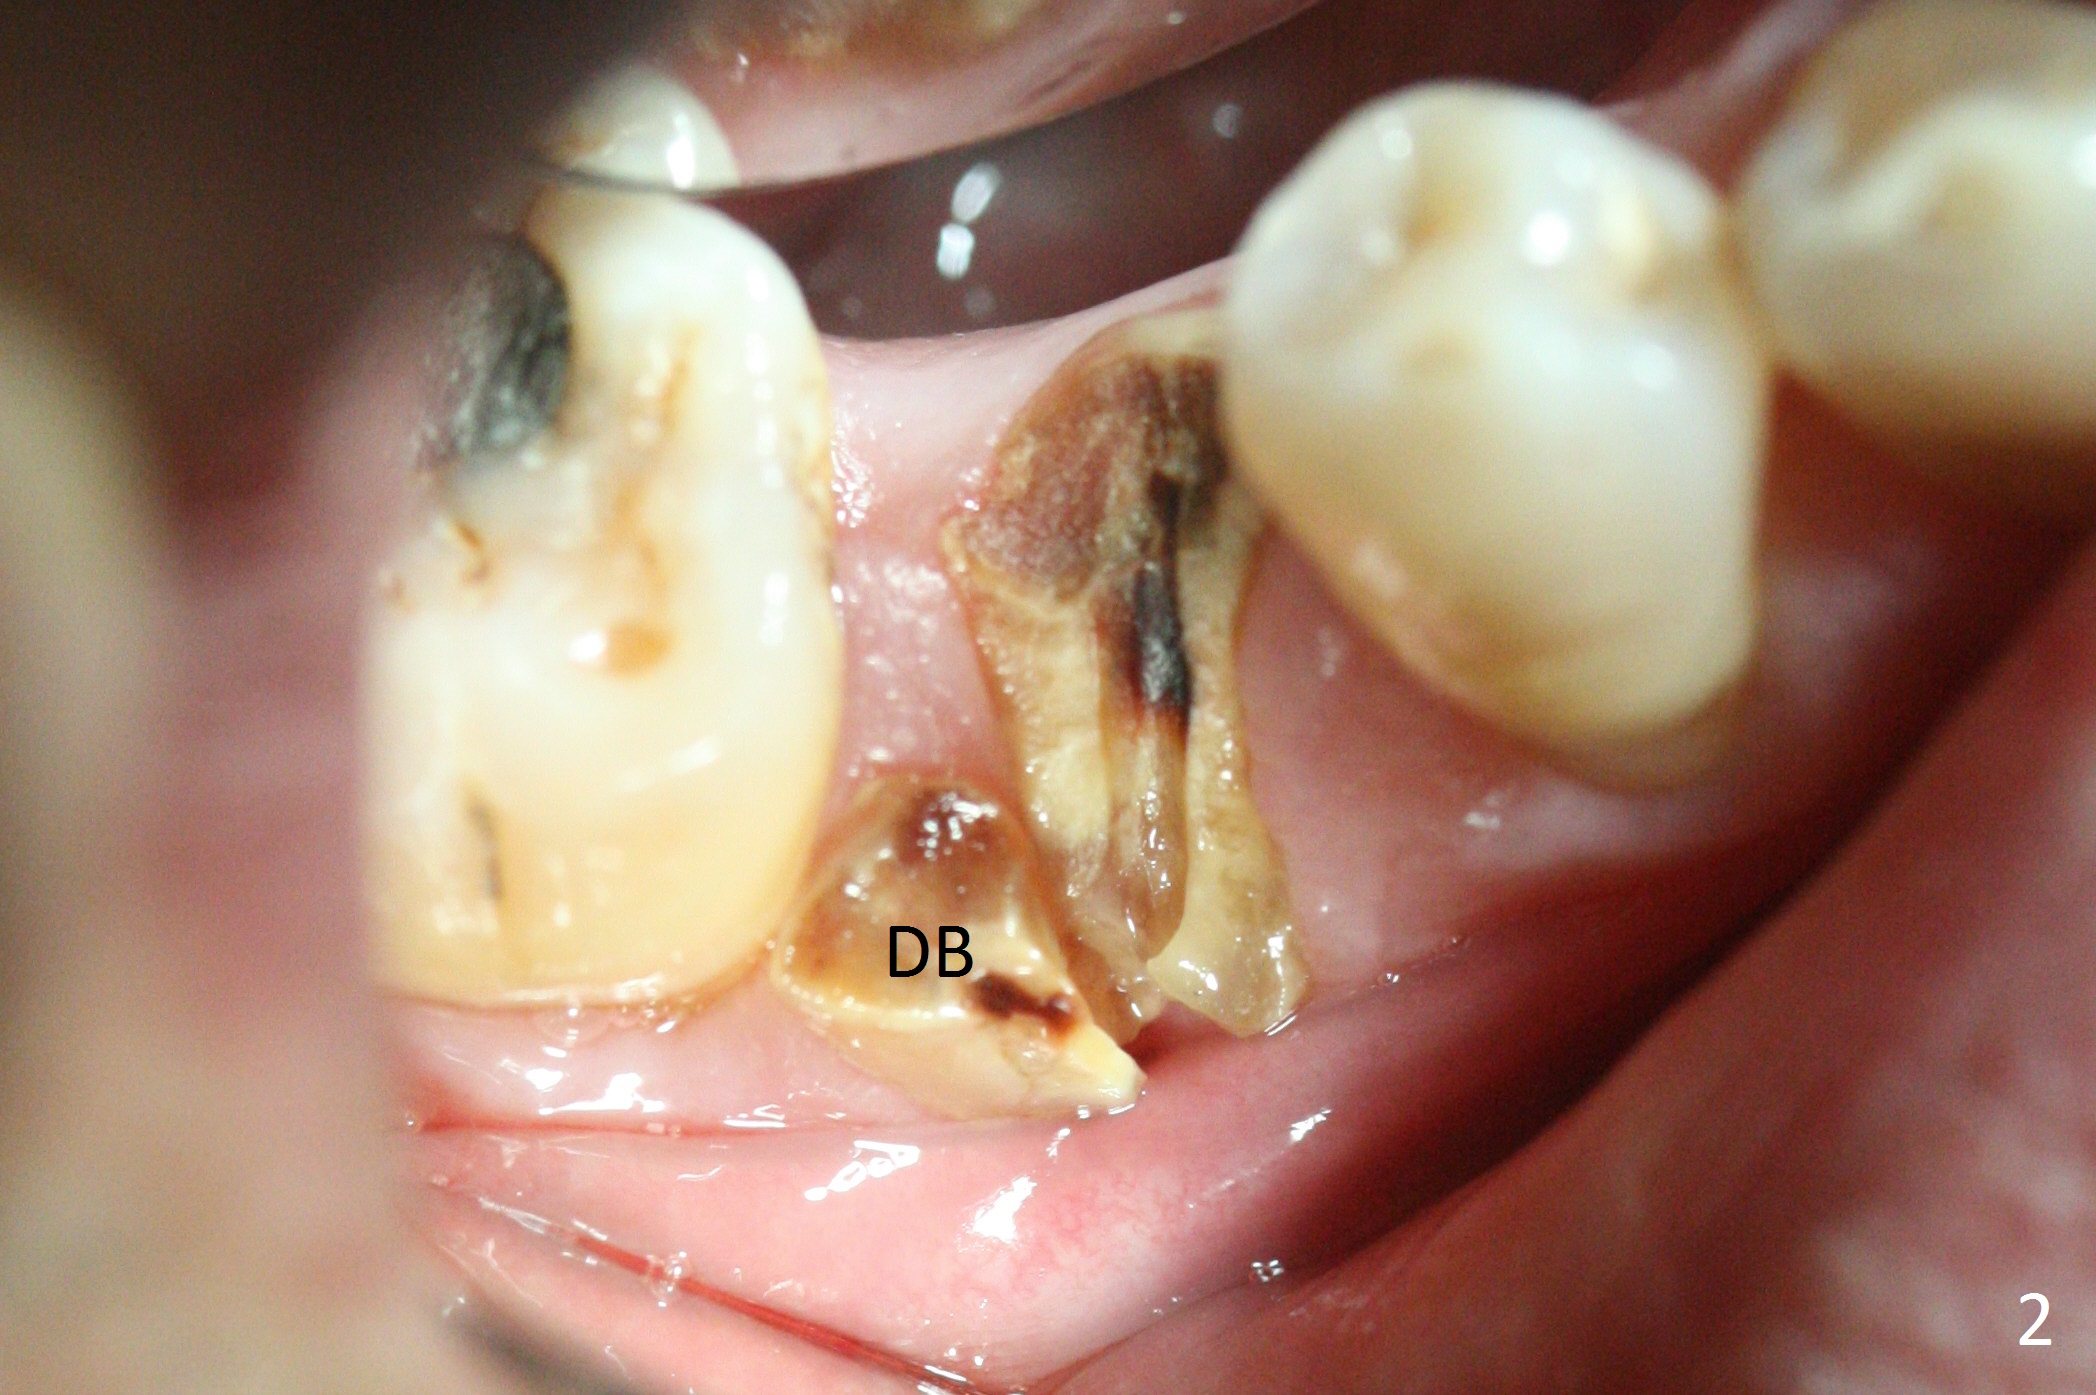

When a 46-year-old man presents with new patient examination, the tooth #29 has root fracture with a crown in place (Fig.1). A year later when he returns for #32 extraction, the crown is lost with displacement of the distobuccal (Fig.2,3 DB) portion of the root. The gingival recession is severe. When the root is removed, an implant will be placed as lingual as possible (Fig.5 white circle). Magic Drill 3.3 mm will be used for osteotomy (without 1.6 mm drill). Trajectory and depth will be tightly controlled while starting and advancing the drilling (one shot). Take PA following partially inserting a 4x11 mm dummy implant.